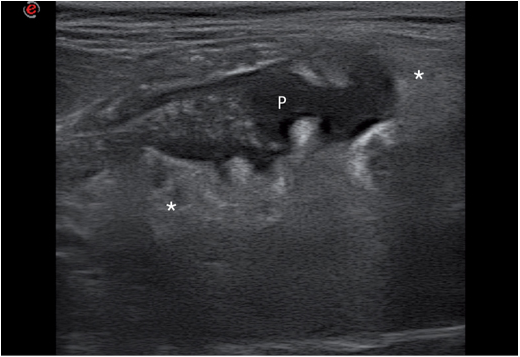

另一个病理过程是全身性脂肪组织炎。它多发于以鱼类为食,摄入过多不包含脂肪酸的动物身上。一例全脂肪炎的公猫的网膜呈现高回声,上面散在分布很多低回声结节。